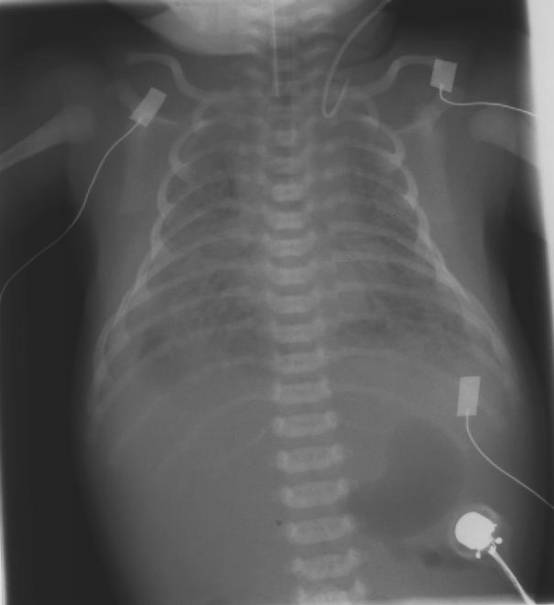

Pat. männlich postpartal

Thorax a.p.:

PC-Winkel beidseits verschattet mit Pleurabegleitschatten rechts im Sinne von Ergussbildungen beidseits, rechts > links. Die Zwerchfellhälften sind nicht abgrenzbar. Das Herz ist nur schemenhaft abgrenzbar, ebenso der Thymusschatten. Korrekte Lage des Tubus. Der von links vorgeführte ZVK ist nach kranial umgeschlagen. Es kommen beidseits fleckige, zum Teil konfluierende Verschattungen zur Darstellung mit teilweise positiven Bronchopneumogramm.

Beurteilung:

Ausgedehnte Mekonium-Aspiration Pneumonie beidseits mit Ergussbildungen beidseits, rechts > links. ZVK-Fehllage.